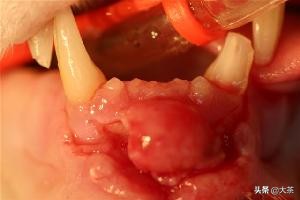

如果猫咪的牙齿断得比较深,那么很可能露出了牙髓,这会给猫咪带来很大的痛苦。

牙髓暴露时,牙齿断面能看到清晰的红点或黑点